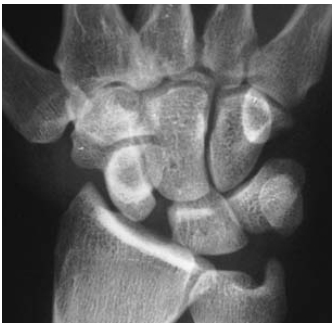

Perilunate dislocation

A

Mech: fall onto hyperextended hand

The four stages of ligamentous injuries in the

wrist are:

* stage I: scapholunate dissociation (less force)

* stage II: perilunate dislocation

* stage III: perilunate dislocation with associated

dislocation/fracture of triquetrum

* stage IV: lunate dislocation.

Xray:

Lateral view - Capitate disloation -> displaced dorsal to lunate

Lunate retains its normal contact with radius

PA view

Capitolunate joint space is obliterated and proximal and distal carpal rows overlap

Clinical:

Wrist swelling and tenderness but gross deformity absent

Mx

Ortho referral for arthroscopy reduction or ORIF